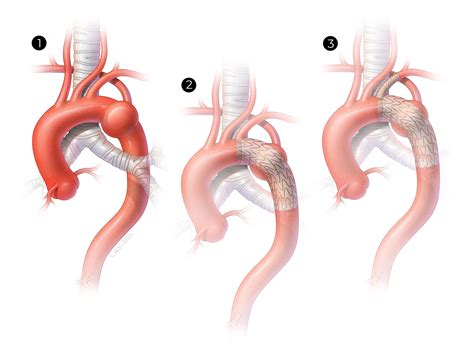

Surgical intervention is indicated for patients with severe symptoms or those at risk of complications. The goal of surgery is to relieve compression of the esophagus and trachea and restore normal blood flow to the right arm. Common surgical procedures include:

• Division and Reimplantation: The aberrant artery is divided and reimplanted into the right common carotid artery or the brachiocephalic trunk.

• Subclavian Artery Transposition: The aberrant artery is transposed to a more normal position, relieving compression on the esophagus and trachea.

Surgical outcomes are generally favorable, with most patients experiencing relief of symptoms and improved quality of life.

📝 Note: Surgical intervention should be performed by experienced vascular surgeons to minimize the risk of complications.